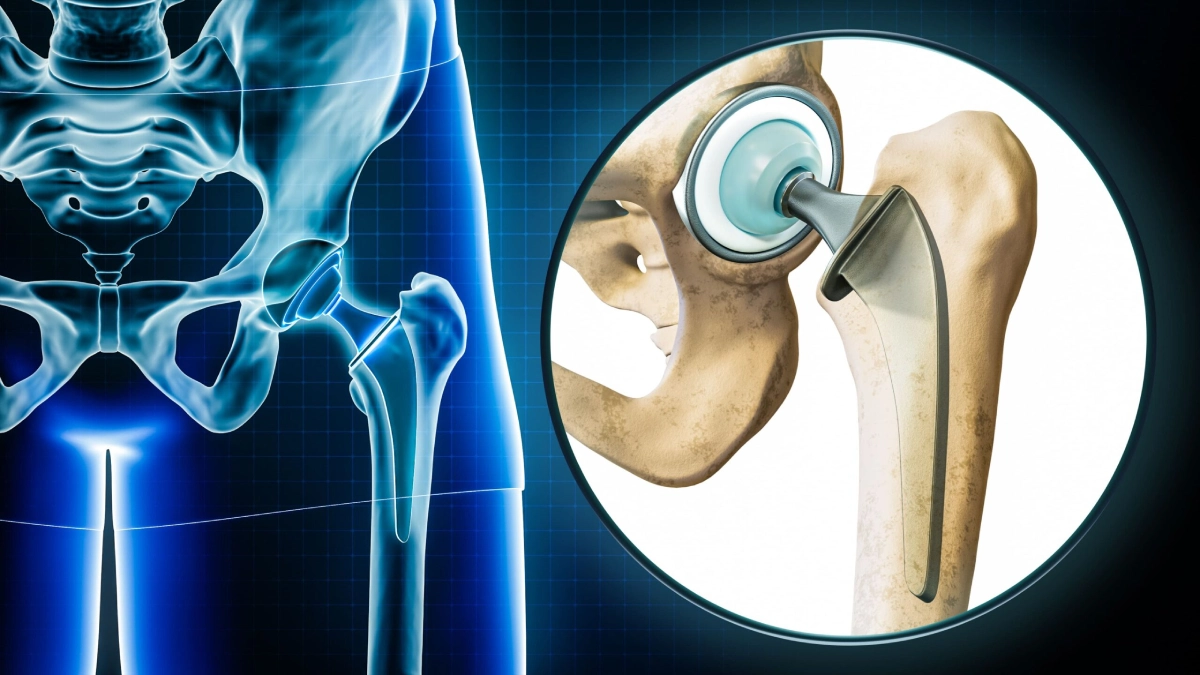

Hip replacement and revision joint replacement

Hip arthritis

Avascular necrosis (AVN)